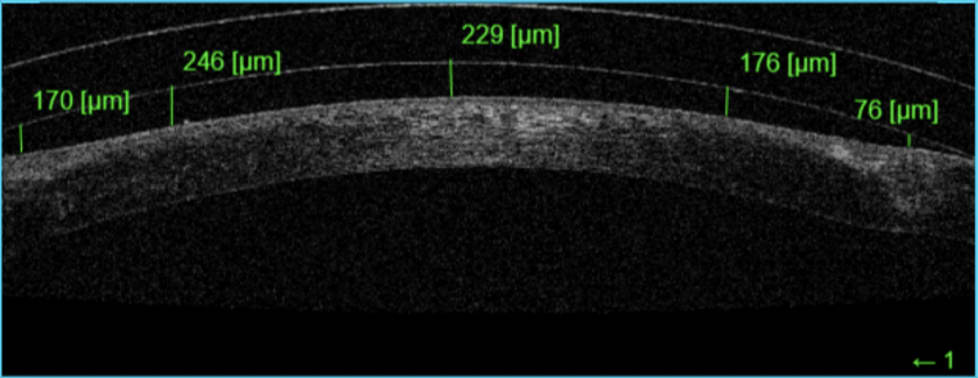

The patient’s hesitation was immediately relieved upon application of the lens. He reported no feeling of pain or discomfort and obtained 20/20 OD after the lens settled. Unfortunately, there was some lens bearing at the elevated suture location with the first fit (Figure 1).

Due to the irregular cornea profile caused by the sutures the lens had to be redesigned to provide clearance in three locations on the eye profile, the apex, the graft interface, and the limbus.